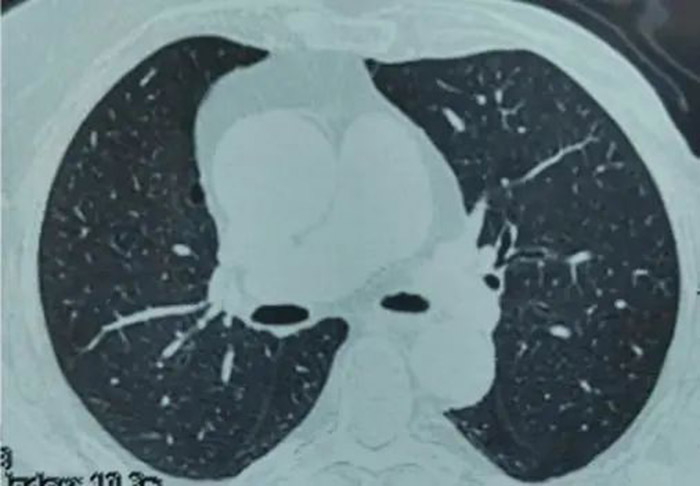

过了3个月阿姨来复查,胸部CT没有看见任何病灶,她的肺结节完全不见了。阿姨高高兴兴的离开了胸外科诊室。